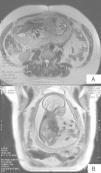

Un mes más tarde, en el seguimiento de la paciente, se realizó una nueva exploración por resonancia magnética en la que, aparte de los hallazgos descritos en la resonancia fetal, fueron detectados agenesia sacra parcial (fig. 2A), vejiga neurógena y espacio presacro disminuido debido a atresia rectal (fig. 2B). Juntos, todos estos hallazgos han sido definidos como síndrome de Currarino.

A) Imagen coronal de resonancia fetal, SSFSE potenciada en T2 en corte consecutivo a la imagen anterior: en este corte se observa una masa hiperintensa que se extiende desde el nivel más inferior del canal medular hasta la región posterior del sacro. B) Imagen axial potenciada en T2 de resonancia del bebé: se identifica agenesia sacra parcial que implica a los últimos cuerpos vertebrales, de morfología anómala y apertura del canal medular que se continua con masa hiperintensa posterior al sacro.